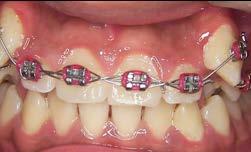

Tratamiento de caninos retenidos superiores en paciente en crecimiento con clase II división 2. Reporte de caso clínico

Los caninos retenidos constituyen una alteración eruptiva frecuente, con mayor prevalencia en la arcada superior. Su etiología es multifactorial y puede interferir con el trayecto normal de erupción, comprometiendo la oclusión y la estética.

Objetivo: Corregir una maloclusión Clase II división 2 mediante tratamiento ortodóntico en un paciente en crecimiento con ambos caninos superiores retenidos. Metodología: Se presenta el caso de un paciente masculino de 12 años, en dentición permanente, con perfil convexo, patrón dolicofacial y Clase II esquelética. Se realizó tratamiento ortodóntico sin extracciones. Para la tracción y alineación de los caninos retenidos se emplearon resortes abiertos (open coil springs) para la creación de espacio. Resultados: